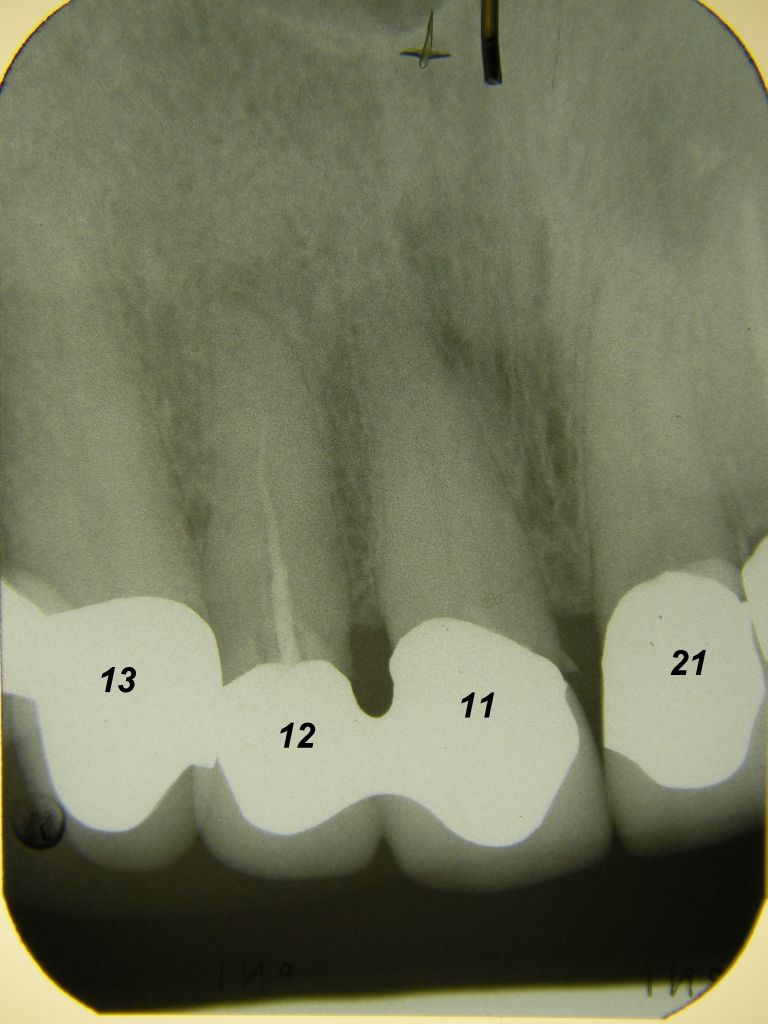

Das etwas dunkle Röntgenbild links(6/2003) zeigt diverse Probleme. Hier interessiert, daß der Zahn 22 (sprich: "zwei", "zwei") am 28.10.05 Schmerzen bereitete, weil der Zahnnerv unter Eiterbildung abgestorben war. Es brauchte 3 medikamentöse Einlagen, bis der Zahn ruhig war und am 18.11.05 eine Wurzelfüllung und einen Titanstift in den Wurzelkanal bekommen konnte. Bei der anschließenden Röntgenkontrolle rechts fiel der schlechte Randschluß der Krone 22 auf. |

Weil auch die anderen Schneidezahnkronen (12-22) durch Randreparaturen und den schlechten Randschluß erneuerungsbedürftig aussahen, wurden 4 Einzelkronen geplant. Vorher hieß es aber noch, die schlechte Wurzelfüllung im Zahn 12 (Röntgenbild links) besser zu machen. Hierfür wurden am 17.2.06 die alten Kronen 11 und 12 entfernt. Rechts das Bild nach Entfernung von alten Füllungen und Karies. | |